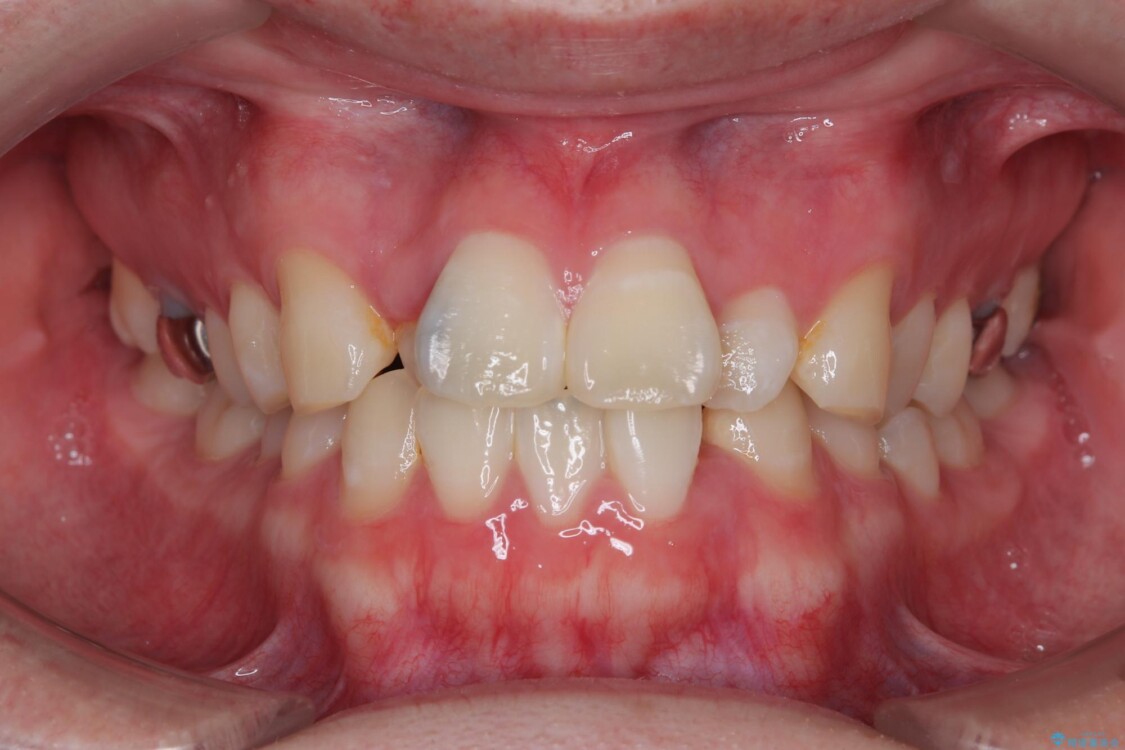

治療後について

適切な診断と装置の選択により、1年という短期間でここまで改善できます。

見た目の美しさだけでなく、将来のむし歯や歯周病リスクを減らすことにもつながる治療です。

治療後

• 1年でここまで変わる!歯列のがたつきと正中のズレを改善した矯正治療(メタルブラケット×MARPE) 治療後画像